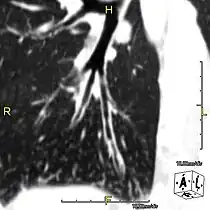

Sagittal CT image showing "tree in bud" appearance of mucous impaction in distal small airways related to primary ciliary dyskinesia

Oblique sagittal CT image showing lower lobe cylindrical bronchiectasis